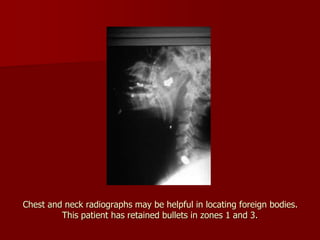

Chest and neck radiographs may be helpful in locating foreign bodies.

This patient has retained bullets in zones 1 and 3.

Chest and neckradiographs may be helpful in locating foreign bodies. This patient has retained bullets in zones 1 and 3.